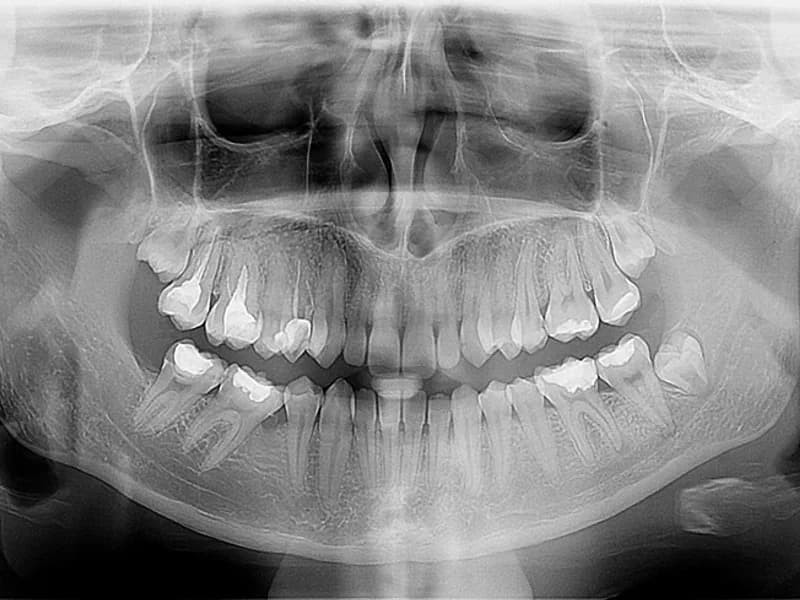

- –Ortopan (panoramska snimka zubi)(Prikazuje sve zube, čeljusti, sinuse i okolne strukture na jednoj slici. Koristi se uređaj Soredex Cranex 3d s minimalnom dozom zračenja. Koristi se za prvi pregled kompletnog stanja zuba, analizu karijesa, upala, cista i kanala, planiranje protetske terapije, kontrolu zubi prije vađenja, sliku za oralnu kirurgiju, kontrolu nicanja kod djece i odraslih.)